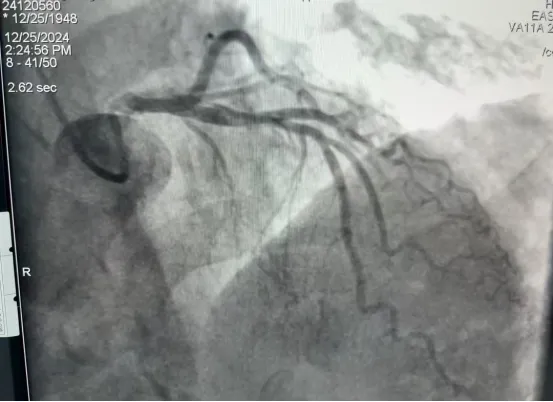

在UG环球国际附属第二医院医疗新技术不断开展、创新的过程中,内一科(神经内科专业、心血管内科)于2024年12月25日完成医院首例心脑血管同台DSA(数字减影血管造影术)。患者因“反复晕厥伴肢体抽搐10余年,且病情加重一周有余”住院,行心脑血管序贯DSA,脑血管造影结果无明显异常,而冠脉造影显示:左前降支近段至中段长节段病变,最重处狭窄约70%。

手术由心血管介入团队和脑血管介入团队序贯进行,采用经桡动脉穿刺造影。整个过程流畅,术后第二天患者正常活动,充分体现了一站式服务的救治理念,也提升了医疗服务质量与可及性,极大地保障了患者权益与健康福祉。开展心、脑血管同台DSA手术,不仅能减少患者手术次数和痛苦、缩短康复周期、减轻经济负担,还能进一步提升医疗技术水平、优化医疗资源利用,同时促进不同专业医生之间的团结、协作。这一成果的取得,得益于医院长期以来对新技术开展、医疗技术创新的重视和投入。同时,神经内科在DSA方面加强了同湖北省第三人民医院神经介入团队的合作。